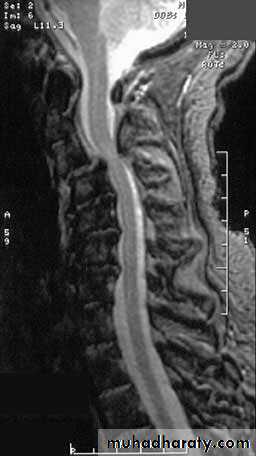

General examinations

ImagingPlain x-rays

Computed tomography (with mylography)

MR imaging

MECHANICAL DERANGEMENTS

Prolapsed lumbar intervertebral discAcute lumbago

Spinal stenosis